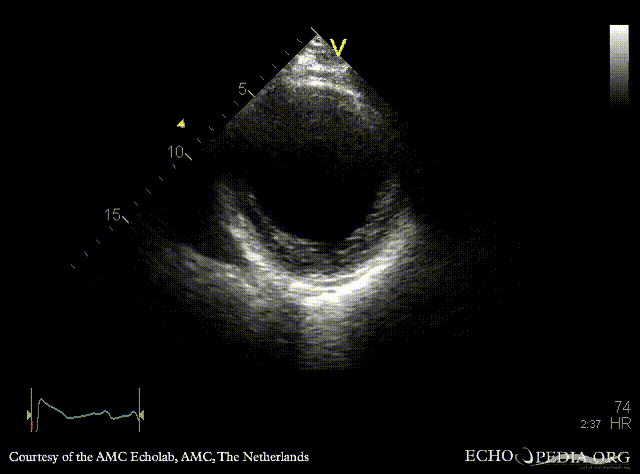

Large aneurysm of LV

A2CH